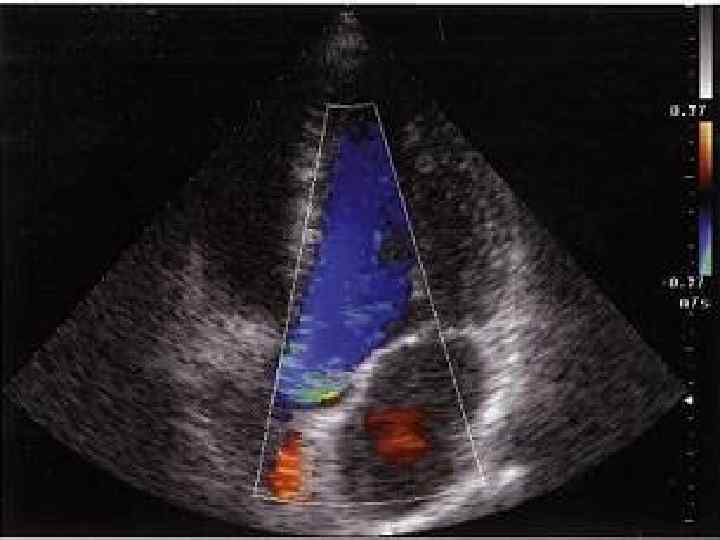

Диастолическая функция ЛЖ Диастолическую функцию ЛЖ оценивают по результатам исследования трансмитраль ногодиастолического кровотока в импульсном допплеровском режиме. Определяют: 1) максимальную скорость раннего пика диастолического наполнения (Vmax Peak E); 2) максимальную скорость трансмитрального кровотока во время систолы левого предсердия 1 (Vmax Peak A); 3) площадь под кривой (интеграл скорости) раннего диастолического наполне ния (MVVTI Peak E) 4) предсердной систолы (MV VTI Peak A); 5) отношение максимальных скоростей (или интегралов скорости) раннего и позднего наполнения (Е/А); 6) время изоволюмического расслабления ЛЖ — IVRT (измеряется при одновременной регистрации аортального и трансмитрального кровотока в постоянно волновом режиме из апикального доступа); 7) время замедления раннего диастолического наполнения (DT).

Vmax Peak E Vmax Peak A Е/А IVRT DT 0, 62 м/с 0, 35 м/с 1, 5 -1, 6 70 -75 м/с 200 мс